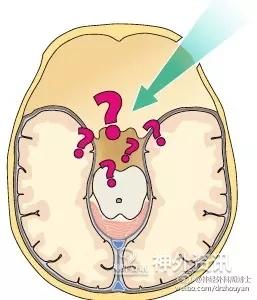

问题 1:由于手术路径需要预先设定,所以手术中病变的分离切除通道无法改变。鉴于此,开颅的位置和范围必须要根据每一个病人、每一个病变的具体情况进行个性化的设定。所以,术前必须要详细分析病人的影像资料。现代先进的手术工具、精准的解剖知识以及术者的经验——这些都是实施keyhole手术的基础。

问题 2:keyhole的第二个缺点就是术中定位定向困难。术前详细分析病变的性质、位置及解剖结构,还有术者的经验,这些都是确保keyhole手术顺利实施的保证。此外,神经导航、术中超声、术中CT和MRI都有助于解决定位定向的问题。